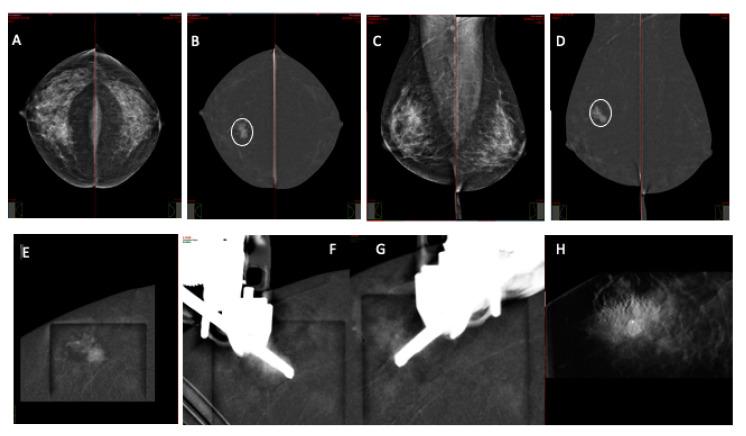

CEM-guided breast biopsy is an advanced diagnostic procedure that takes advantage of the ability of CEM to enhance suspicious breast lesions. The aim pf this paper is to describe a single-center retrospective experience on CEM-guided breast biopsy in terms of procedural features and histological outcomes. 69 patients underwent the procedure. Patient age, breast density, presentation, dimensions, and lesion target enhancement were recorded. All the biopsy procedures were performed using a 7- or 10-gauge (G) vacuum-assisted biopsy needle. The procedural approach (horizontal or vertical) and the decubitus of the patient (lateral or in a sitting position) were noted. A total of 69 patients underwent a CEM-guided biopsy. Suspicious lesions presented as mass enhancement in 35% of cases and non-mass enhancement in 65% of cases. The median size of the target lesions was 20 mm. The median procedural time for each biopsy was 10 ± 4 min. The patients were placed in a lateral decubitus position in 52% of cases and seated in 48% of cases. The most common approach was horizontal (57%). The mean AGD was 14.8 mGy. At histology, cancer detection rate was 28% (20/71). CEM-guided biopsy was feasible, with high procedure success rates and high tolerance by the patients.

对比增强钼靶(CEM)引导下的乳腺活检是一种先进的诊断程序,它利用了CEM增强可疑乳腺病变的能力。本文的目的是描述在一家单中心进行CEM引导下乳腺活检的回顾性经验,包括操作特点和组织学结果。69例患者接受了该手术。记录了患者的年龄、乳腺密度、表现、尺寸以及病变的目标增强情况。所有活检操作均使用7号或10号真空辅助活检针进行。记录了操作方法(水平或垂直)以及患者的体位(侧卧位或坐位)。共有69例患者接受了CEM引导下的活检。可疑病变在35%的病例中表现为肿块增强,在65%的病例中表现为非肿块增强。目标病变的中位大小为20毫米。每次活检的中位操作时间为10±4分钟。52%的病例中患者采取侧卧位,48%的病例中患者采取坐位。最常见的方法是水平法(57%)。平均腺体剂量(AGD)为14.8毫戈瑞。在组织学检查中,癌症检出率为28%(20/71)。CEM引导下的活检是可行的,手术成功率高,患者耐受性好。